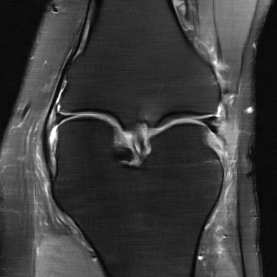

Deep Learning (DL) methods have shown promising results for solving ill-posed inverse problems such as MR image reconstruction from undersampled $k$-space data. However, these approaches currently have no guarantees for reconstruction quality and the reliability of such algorithms is only poorly understood. Adversarial attacks offer a valuable tool to understand possible failure modes and worst case performance of DL-based reconstruction algorithms. In this paper we describe adversarial attacks on multi-coil $k$-space measurements and evaluate them on the recently proposed E2E-VarNet and a simpler UNet-based model. In contrast to prior work, the attacks are targeted to specifically alter diagnostically relevant regions. Using two realistic attack models (adversarial $k$-space noise and adversarial rotations) we are able to show that current state-of-the-art DL-based reconstruction algorithms are indeed sensitive to such perturbations to a degree where relevant diagnostic information may be lost. Surprisingly, in our experiments the UNet and the more sophisticated E2E-VarNet were similarly sensitive to such attacks. Our findings add further to the evidence that caution must be exercised as DL-based methods move closer to clinical practice.